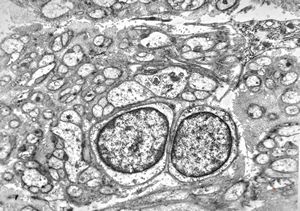

M, 11y. | mycosis fungoides v.s. - cerebriform nucleus of Sézary cell

F, 57y. | mycosis fungoides … cerebriform nucleus of Sézary cell

F, 37y. | mycosis fungoides … cerebriform nucleus of Sézary cell

M, 70y. | mycosis fungoides - Sézary cell